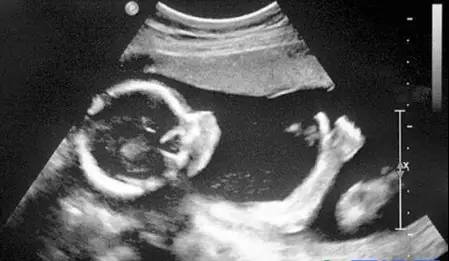

B超

像挑西瓜前敲一敲

B超的原理是用超声波穿透人体,当声波遇到人体组织时会产生反射波,通过计算反射波成像。就像挑西瓜一样,边敲边看显示病灶情况。